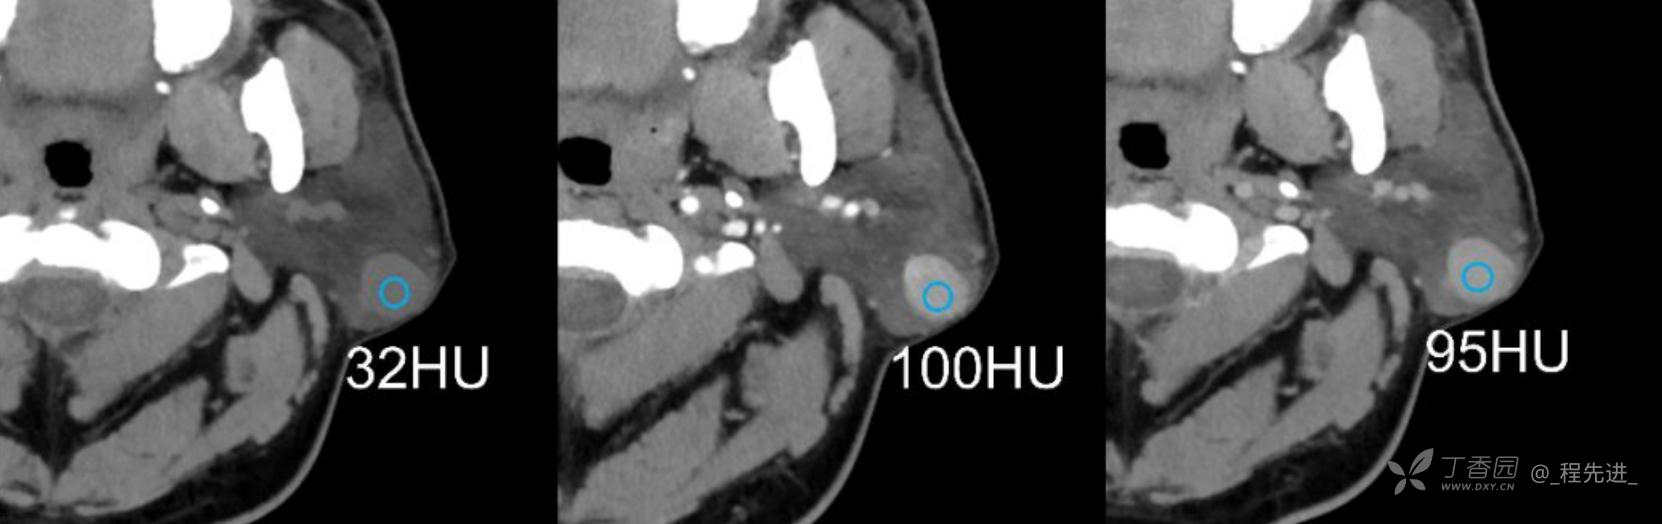

患者性别:男

患者年龄:38岁

简要病史:病程1年,1年前发现左耳后肿物,无发热疼痛不适,未见明显增大,入院

辅助检查:实验室各项指标未见明显异常